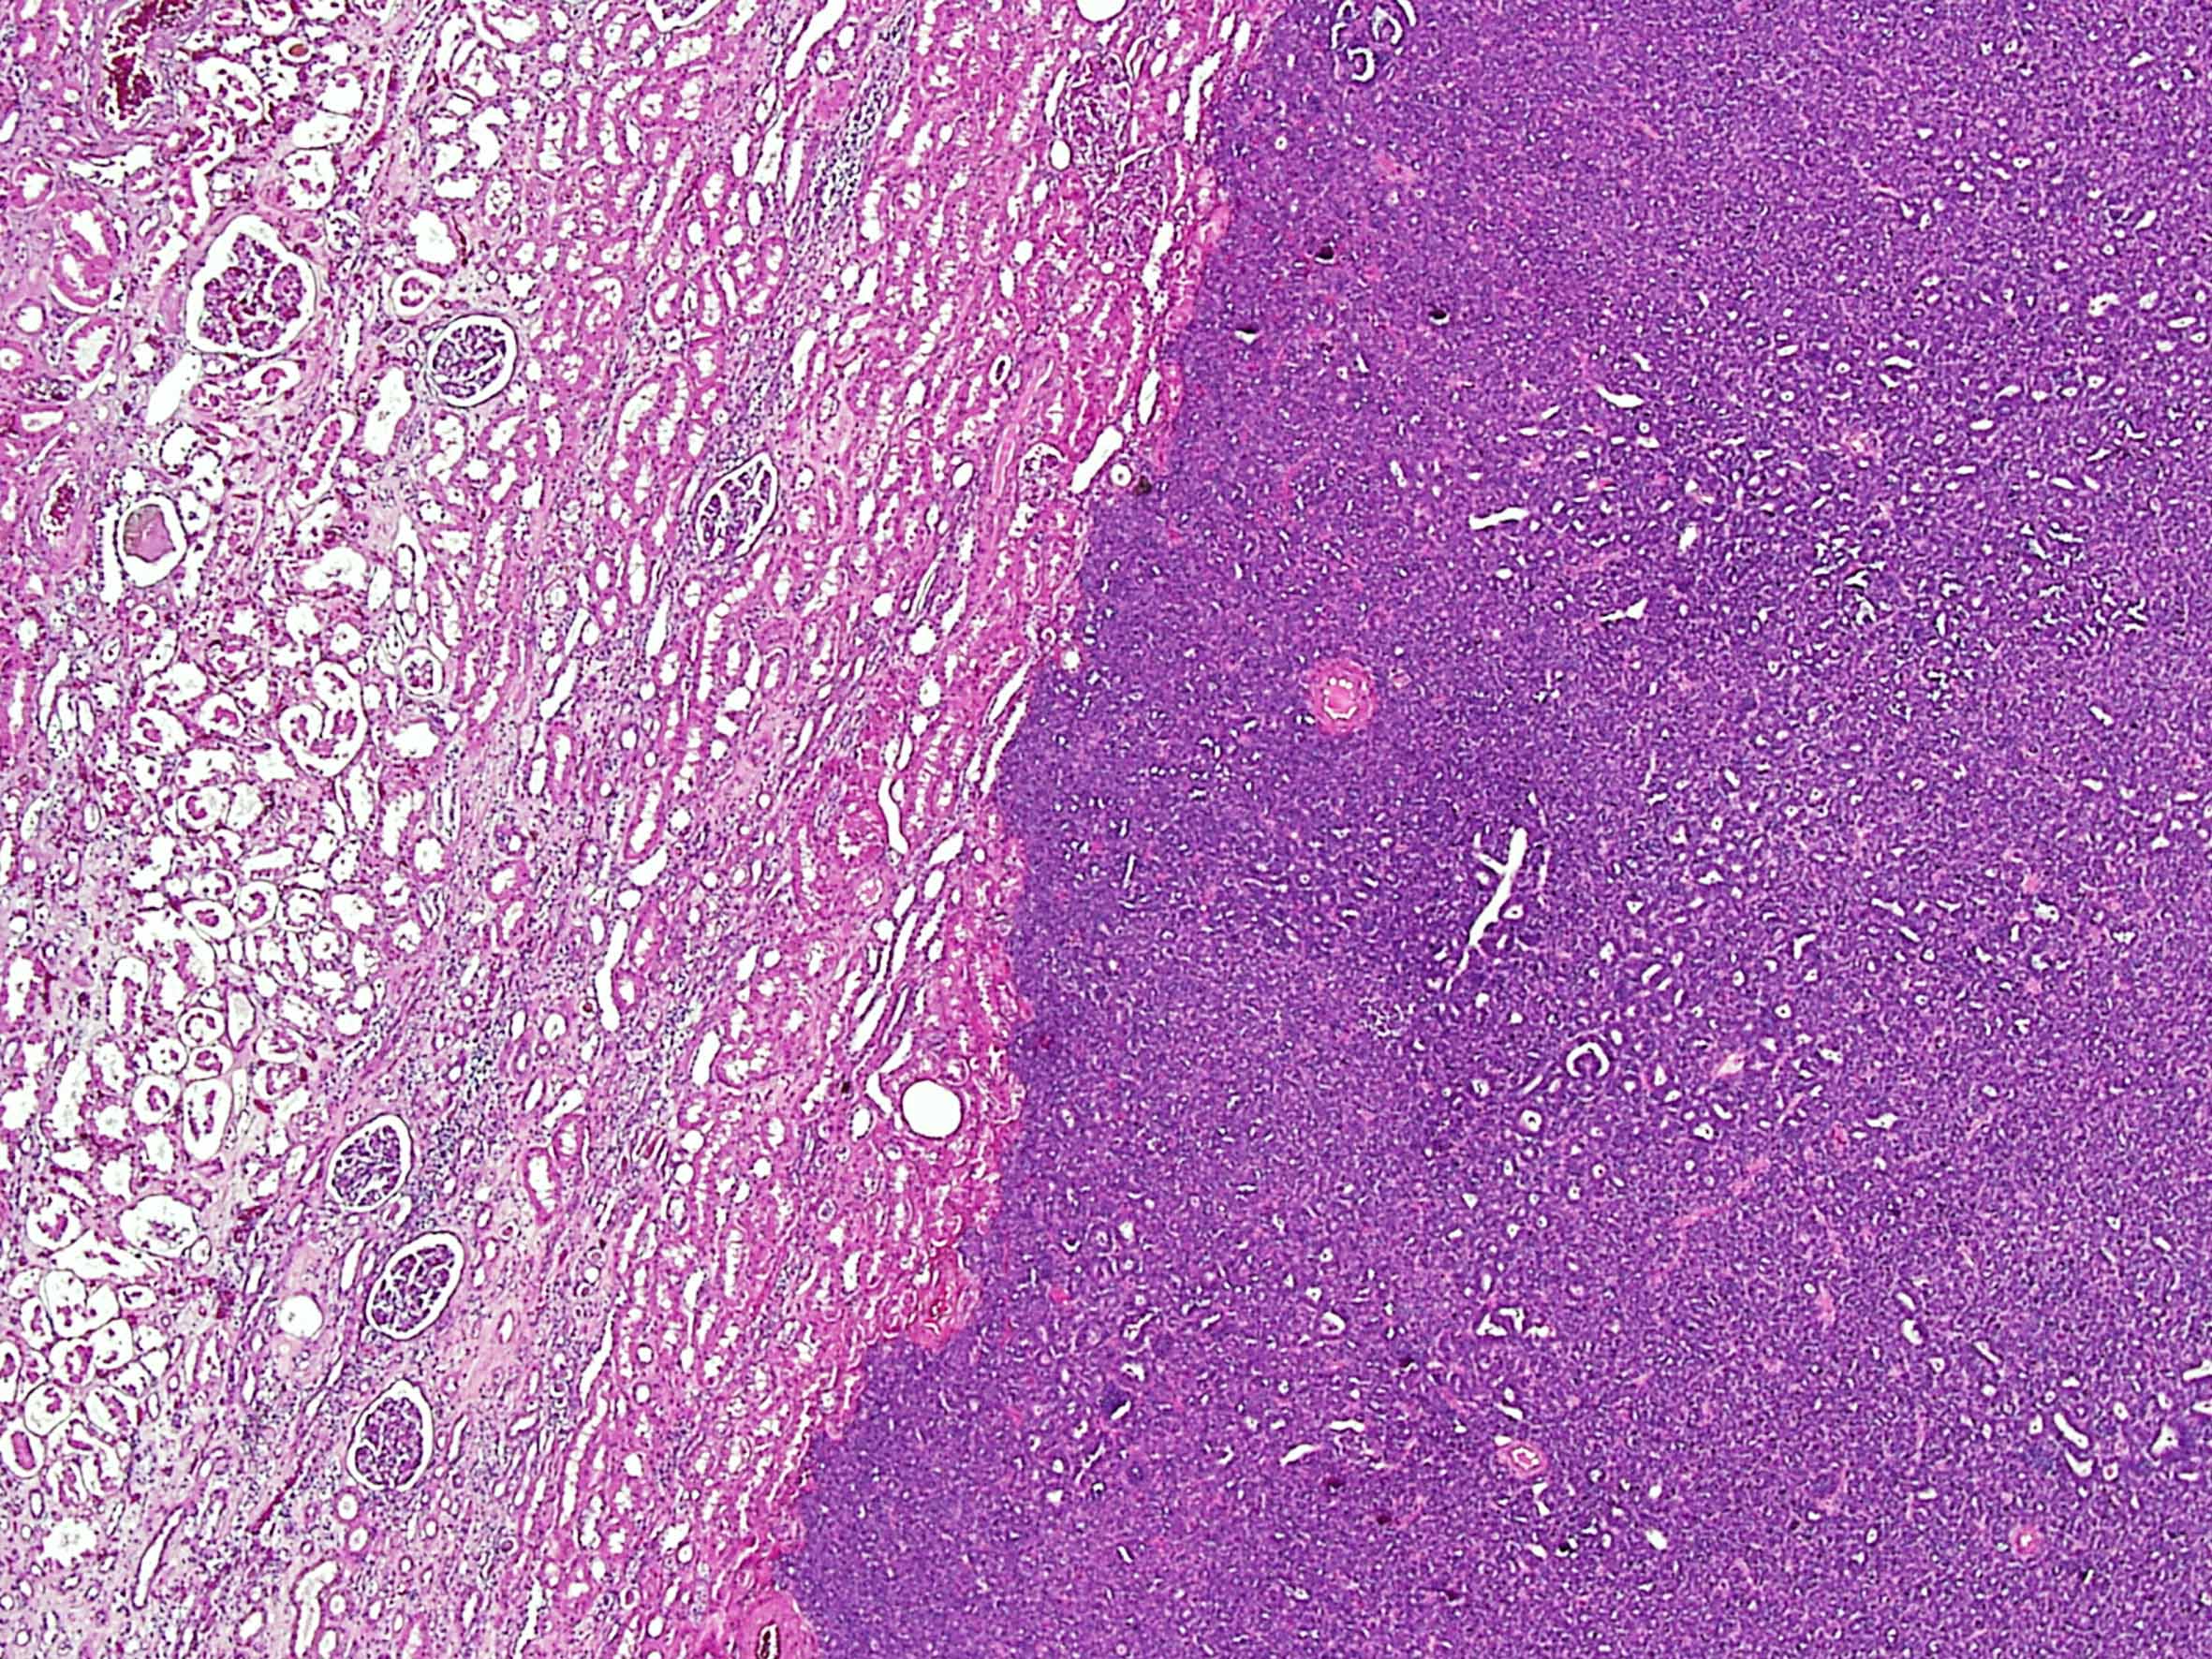

Metanephric adenoma